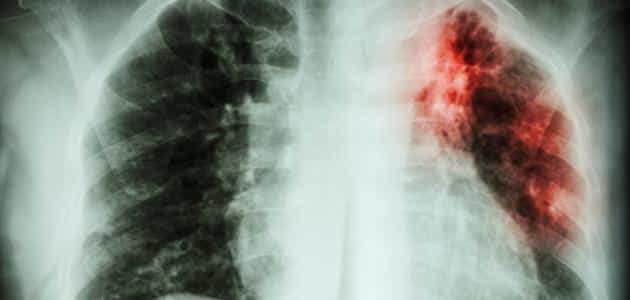

أسباب تليف الرئة

هناك باقة من الأسباب الثانوية التي تتعلق بمختلف الأمراض الروماتيزمية والتي من أشهرها مرض التصلب الجلدي وهذا المرض يعتبر نادر وكذلك بعض أمراض الروماتيد التي قد يصاب بها الناس، علاوة على المرضى المصابين بالتهابات العضلات.

الجدير بالذكر أن الطبيبة قد أشارت إلى وجود مجموعة من الأمراض المناعية والتي من أبرزها التهاب العضلات الجلدي علاوة على مرض الذئبة ولكن الأغلبية تكون مع التصلب الجلدي والتهاب العضلات فهذا يكون السبب وراء تليف الأنسجة.